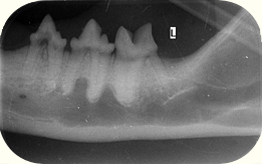

| Wichtig ist bei TR (FORL) jedenfalls eine genaue Diagnose durch intraorale Zahnröntgen. Denn Dental-Röntgen eröffnet eine neue Therapie bei TR (FORL). 67% der Katzen leiden unter röntgenologisch verifizierbaren TR (FORL). Nur 12,6 % der TR (FORL) sind klinisch sichtbar. Das Dentalröntgen eröffnet aber auch eine neue therapeutische Möglichkeit. Viele beginnende Wurzelresorptionen unter dem Zahnhals und sogenannte "ghost roots" werden ohne Röntgen übersehen. |

Zudem ermöglicht ein Dentalröntgen die Differenzierung zwischen den 2 wichtigsten Typen der Wurzelpathologie bei der Katze:

Typ 1: relativ normale Wurzel mit erkennbarem parodontalen Ligamentspalt und

Typ 2: Wurzelumbau („root replacement“) ohne Ligamentspalt, mit knochendichter Wurzel.